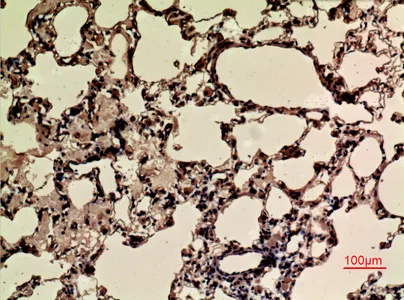

CD68 Rabbit Polyclonal Antibody

Cat: APRab08436

Size1:50μl Price1:$118

Size2:100μl Price2:$220

Size3:500μl Price3:$980

Size2:100μl Price2:$220

Size3:500μl Price3:$980